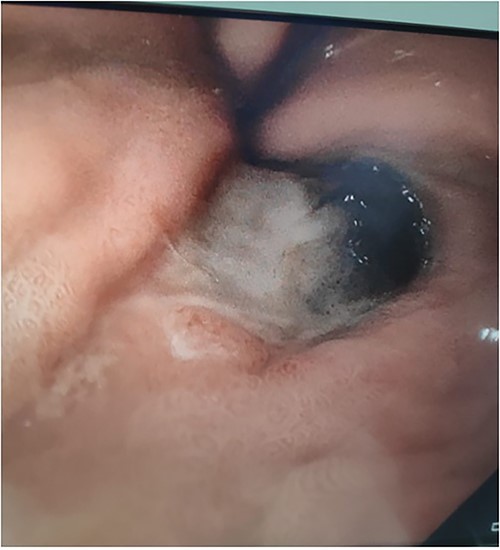

A 71-year-old female presented to a rural hospital with generalised abdominal pain and fevers in the context of a fall 3 days prior on a background of a myeloproliferative disorder, type 2 diabetes mellitis, cerebrovascular accident (CVA), chronic kidney disease and hypertension. The patient was tachycardic, febrile and had a peritonitic abdomen on examination. A computed tomography (CT) scan demonstrated a subcapsular splenic haematoma and haemoperitoneum. Urgent laparotomy revealed a sub-phrenic abscess and infected splenic haematoma for which uncomplicated splenectomy was performed. The postoperative course was initially uncomplicated with the patient tolerating diet, opening bowels and mobilising appropriately. Day 3 postoperatively, the patient developed burning central chest pain for which cardiac investigations were unremarkable. The patient received two units of packed red blood cells for a haemoglobin of 82 and intravenous proton pump inhibitor. The patient subsequently had a 250-ml episode of haematemesis and became haemodynamically unstable. Urgent upper gastrointestinal endoscopy demonstrated oesophageal necrosis from 20 cm from the teeth to the proximal margin of the gastro-oesophageal junction, diffuse bleeding from the distal oesophagus and adherent clot at the gastric fundus. The patient was transferred to a tertiary centre where repeat endoscopy demonstrated oesophageal necrosis and a well-circumscribed area of gastric fundus necrosis (see Figs 1–3) at the site of the adherent clot. Oesophageal biopsy demonstrated herpes simplex virus (HSV) 1-associated oesophagitis. Post-endoscopy the patient developed renal failure and failed extubation in intensive care. Given the multiple comorbidities of the patient and declining functional status prior to admission the family felt further invasive measures would not be in her best wishes. The patient was transitioned to comfort care and passed away the following day.

Upper gastrointestinal endoscopy image demonstrating oesophageal necrosis.